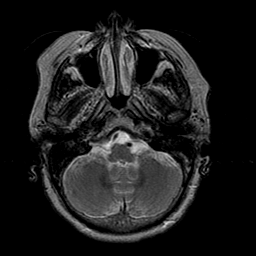

Stroke:T2-weighted MR #1 -- Slice #4

[Home][Help][Clinical] Slice 4